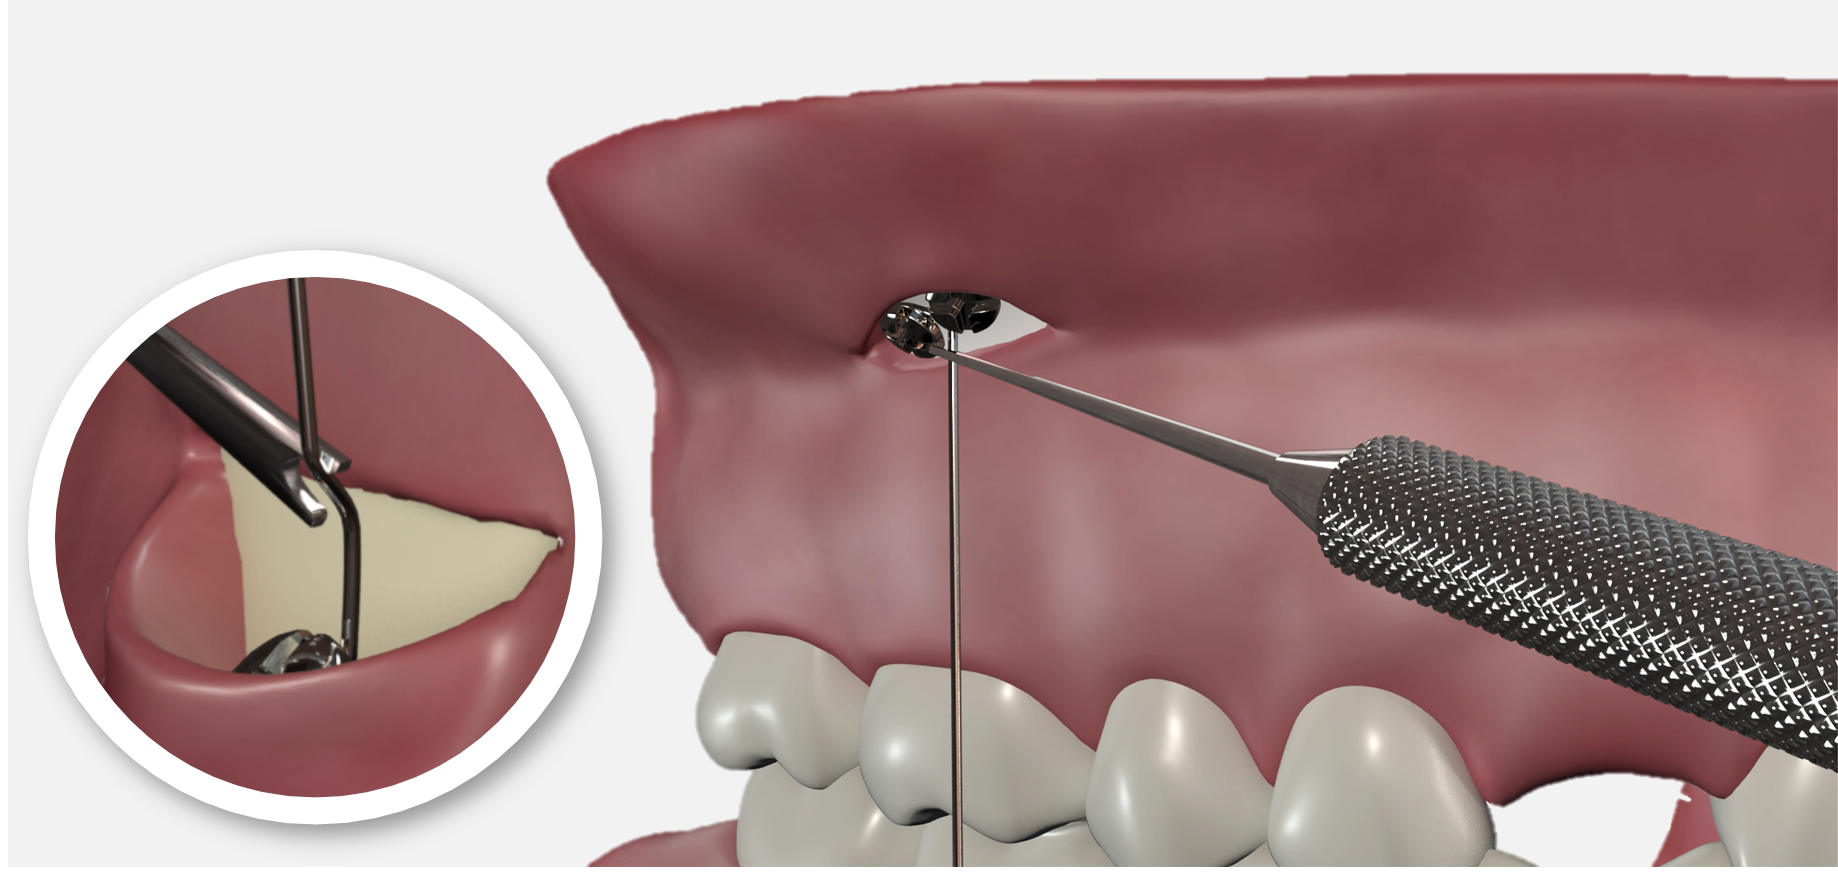

- Réalisation d'une baïonnette au niveau du trait d'incision (fond de vestibule)

En deçà, le fil est plaqué contre l’os, au-delà il doit longer la gencive sans appui.

Elle est réalisée à l’aide de l’instrument dédié dont la gorge coiffe le fil et qui est tourné d’ un huitième à un quart de tour environ afin de compenser l’épaisseur de muqueuse.

Cette manoeuvre apparaît à l’usage la plus délicate à réaliser de toute la procédure de mise en place d’un CT8 car un fil trop écarté gênera à la longue la muqueuse labiale ou jugale, alors qu’un fil trop serré comprimera la gencive d’une manière excessive.